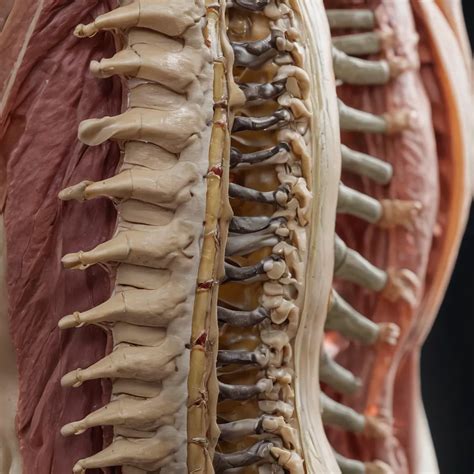

Hey guys, let’s dive into a topic that affects a lot of us at some point: degenerative L1 L2 issues in the lumbar spine. Now, I know that sounds a bit intimidating, but understanding what’s happening with your lower back can be the first step towards feeling better. When we talk about degeneration, we’re essentially referring to the natural wear and tear that happens to our spine as we get older. It’s a process that affects the vertebrae (those are your spinal bones), the discs (the spongy cushions between them), and the joints that connect everything. The L1 and L2 vertebrae are part of your upper lumbar spine, and issues here can lead to a variety of symptoms. We’re talking about pain, stiffness, and sometimes even issues with how your legs function. It’s not just about aging, though. Factors like genetics, previous injuries, and even your lifestyle can play a significant role in how and when this degeneration occurs. So, what exactly is going on at these L1 and L2 levels? It typically involves a combination of changes. The intervertebral discs between L1 and L2 might start to lose their height and hydration, becoming less effective at absorbing shock. This is often referred to as degenerative disc disease . You might also see changes in the facet joints , which are the small joints at the back of your spine that allow for movement. These can develop osteoarthritis , meaning the cartilage that cushions them wears down, leading to pain and stiffness. In more advanced cases, you might see bone spurs (osteophytes) forming, which are extra bits of bone that can sometimes press on nerves. This entire process, this degeneration of L1 L2 , is a complex one, but understanding the basics is key to managing it effectively. It’s crucial to remember that while degeneration is common, it doesn’t always mean constant pain or disability. Many people have degenerative changes without significant symptoms. However, when symptoms do arise, they can significantly impact your quality of life, making everyday activities feel like a monumental task. We’ll explore the causes, symptoms, and most importantly, the management strategies in more detail, so stick around!